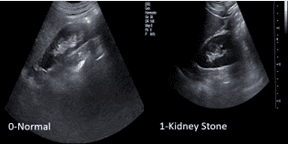

Abstract: Urolithiasis, commonly known as kidney stones (KS), can have serious health implications. In 2019, around 115 million people around the world suffered from this disease. It is extremely important that the disease be diagnosed quickly. Among all the possible diagnostic imaging options, ultrasound is the safest option, as it has no risk of radiation. The goal of this study is to create a system that will detect kidney stones from ultrasound images. The dataset used in this research had 2 classes: normal (4414) and kidney stone (5002), in total 9416 images. The dataset was preprocessed applying proper methods such as resizing, rescaling, and center cropping and then split into train, validation, and test sets. We deployed four pretrained deep learning models, which are DenseNet201, ResNet50, InceptionV3, and MobileNetV3. Methods like MixUp and CutMix, known as augmented regularization, were used to make the model more robust. Hyperparameter tuning was done for optimal results. The layers of the pretrained model were frozen, and on top of them our CNN model was placed. The research was conducted using two methods: one where pretrained models were only used for feature extraction and another where pretrained models were fine-tuned for training. The highest accuracy of 99.73% was achieved by DenseNet. The model’s output prediction has been explained by using saliency maps. After 1000 iterations, the 99% confidence interval for the model is [0.993,0.999]